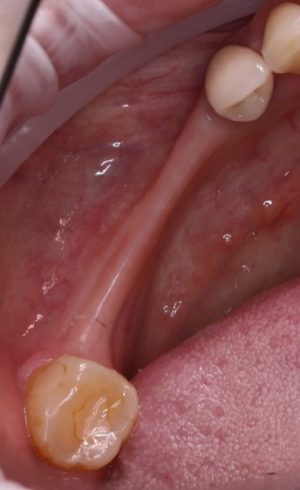

Если нет задачи ставить импланты — зачем открывать и скелетировать альвеолярный гребень? Чем больше операционная рана, тем больше потом будет проблем. Будьте рациональны:

Как видите, я перенес разрез вестибулярно, примерно в проекции предполагаемого субантрального доступа. Таким образом, я получаю тот же обзор при меньшей по площади ране. Это безопаснее. Такой доступ очень просто и легко зашивается, рана заживает быстрее и с минимальным дискомфортом. Кроме того, слизистая оболочка вершины альвеолярного гребня, где мы будем потом делать следующий разрез для установки имплантов, осталась неповрежденной, мы не оставили на ней рубцов, которые могут осложнить заживление при повторном входе для установки имплантов.